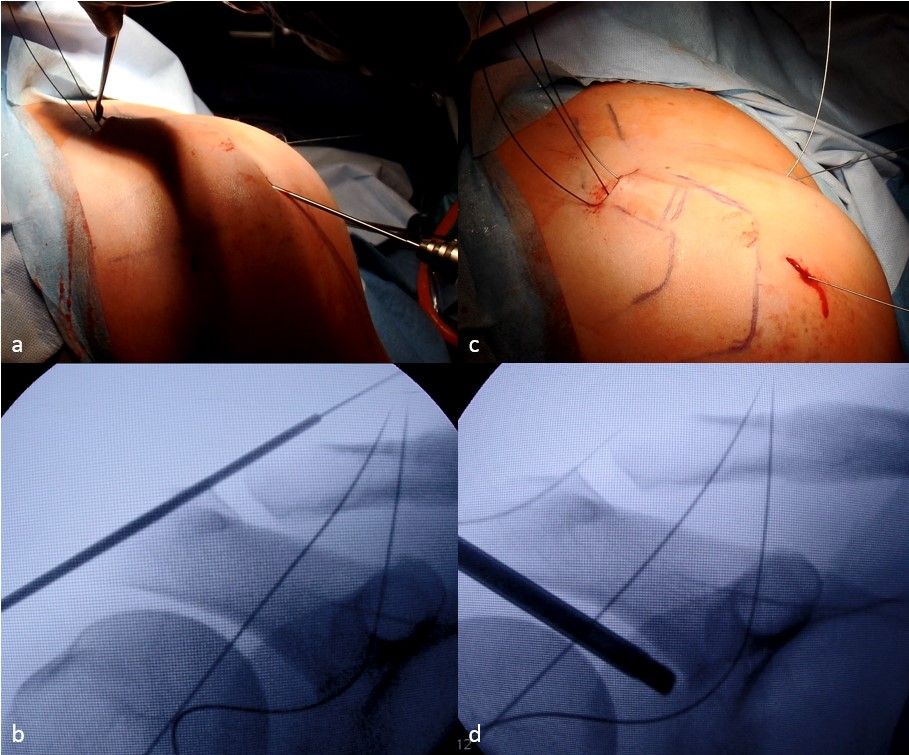

Clavicular and acromial drilling

For horizontal stabilization, a percutaneous acromioclavicular cerclage is used using a classic anterior cruciate ligament (ACL) drill guide. Therefore, the marking hook is placed via the superior incision behind the clavicle while the drill sleeve is introduced through the anteroinferior portal. The first drilling is performed transclavicular from anterior to posterior.

A 1.25 mm K-wire is placed through the clavicle under image intensifier control and overdrilled with a 2.7 mm cannulated drill bit. The K-wire can then be removed, and a nitinol suture passer is inserted via the cannulated drill bit and retrieved at the clavicular incision. For transacromial drilling another 1.25 mm K-wire is used and drilled from lateral-caudal to medial-cranial and anterior of the AC joint. A transarticular drilling can be avoided by caudalization of the clavicle. After overdrilling with a 2.7 mm cannulated drill bit and removal of the K-wire a nitinol suture passer is inserted and retrieved via the clavicular incision.